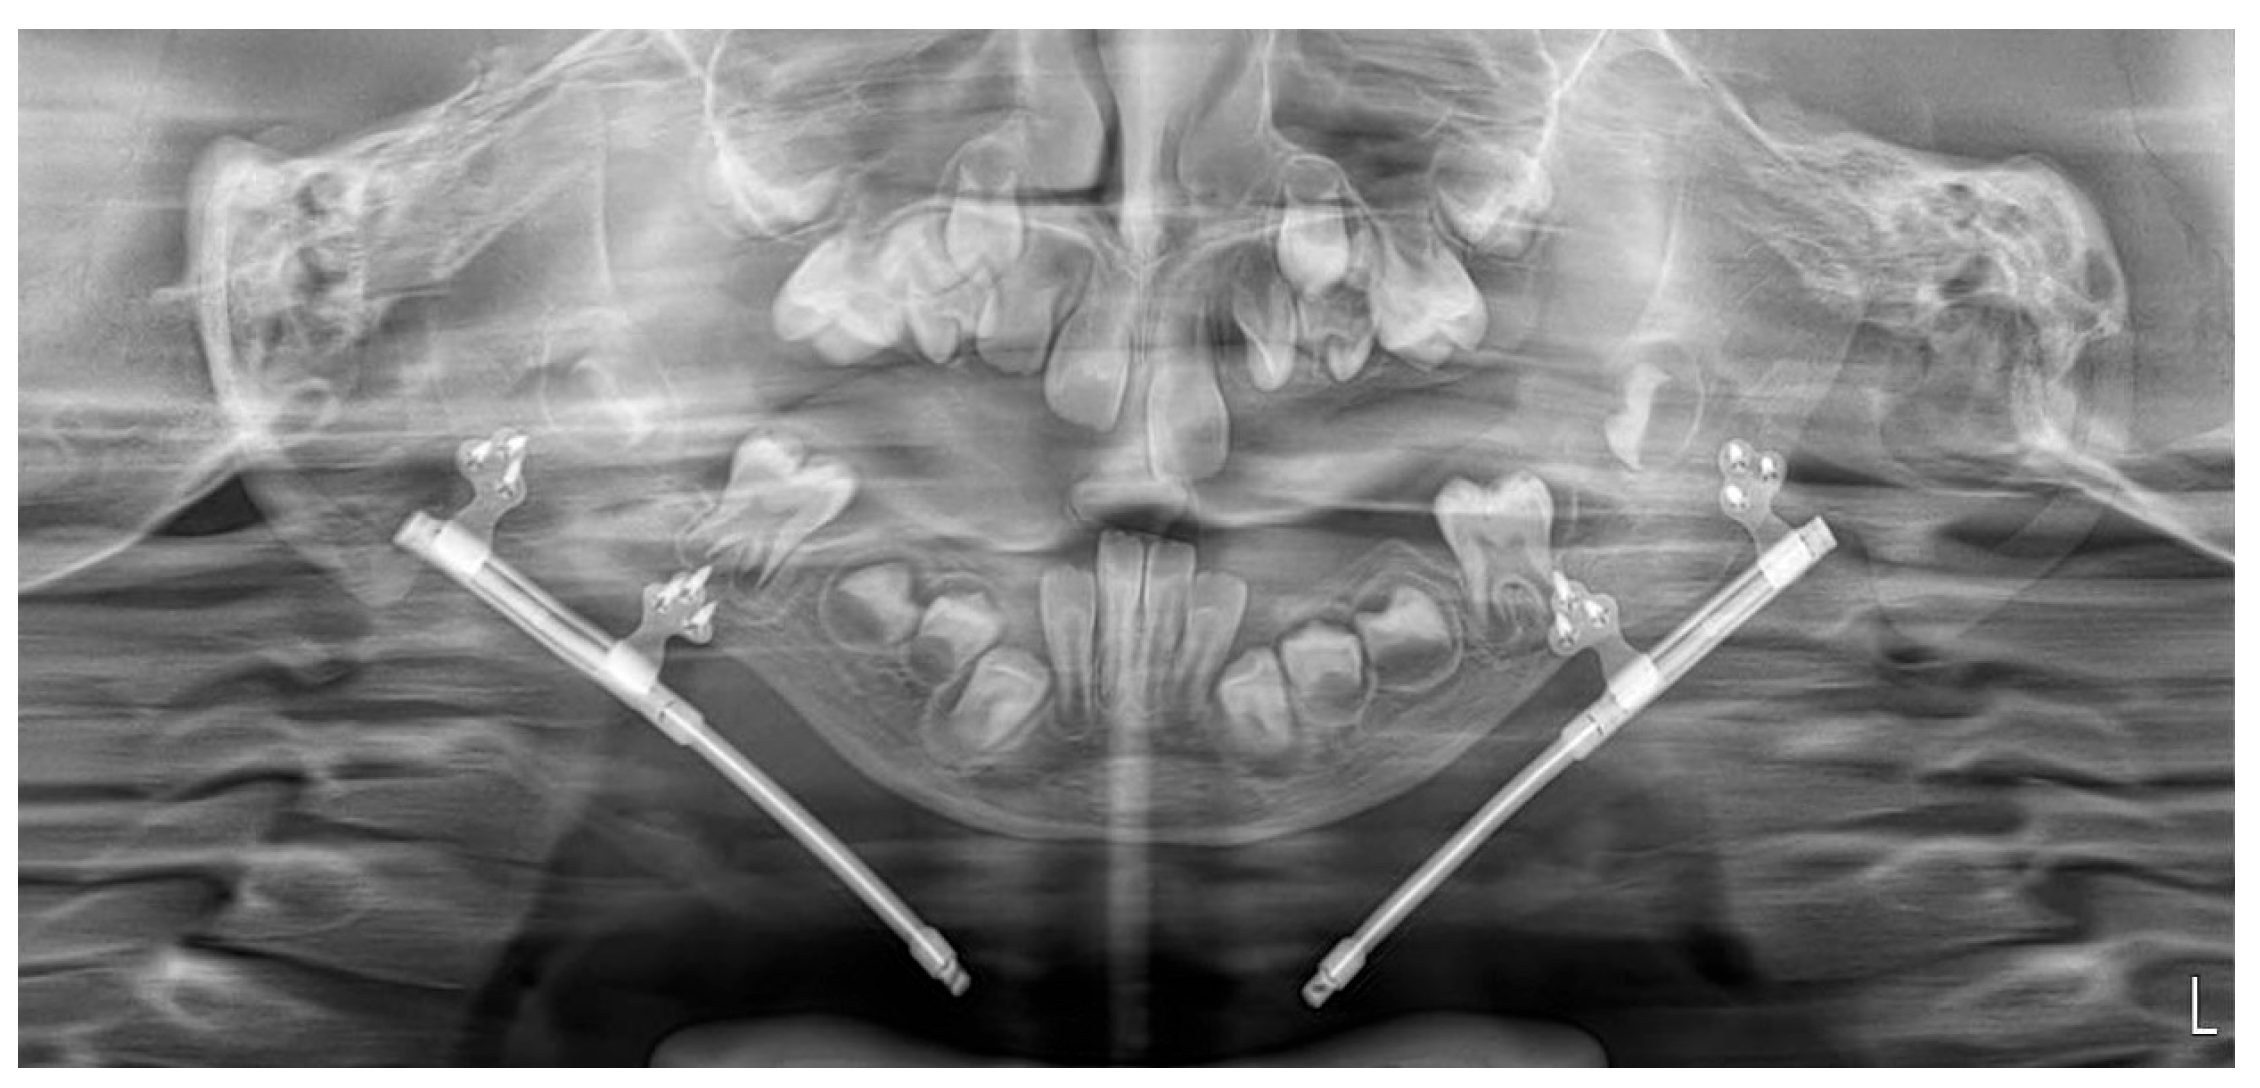

Postoperatively, the patient was monitored in the intensive care unit during the immediate postoperative period. She was transferred to the pediatric surgery postoperative care ward on the first postoperative day. She received amoxicillin/clavulanic acid 0.6 g intravenously every 8 h, administered according to the standard perioperative prophylactic protocol. The radiographs confirmed accurate positioning of the distractors according to the preoperative plan (Figure 5).

Figure 5. Panoramic radiograph performed on the first postoperative day showing appropriate positioning of the osteotomy line and an adapted distractor.

N/A: not available; ICU: intensive care unit. Representative panoramic radiographs and ultrasonographic images for days 6, 21, 42 (week 6), and week 16 post-distraction are shown in Figure 5, Figure 7 and Figure 8.